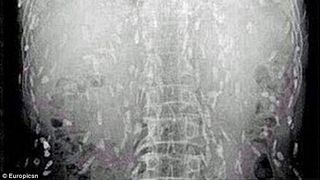

La o simpla radiogafie, medicii si-au dat seama ca trupul chinezului este infectat cu viermi.  Bietul barbat s-a ales cu acesta contaminare din cauza ca a consumat prea mult peste.